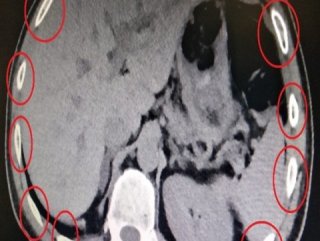

Yakalanan 2 kişinin midesinden 100 paket uyuşturucu çıktı